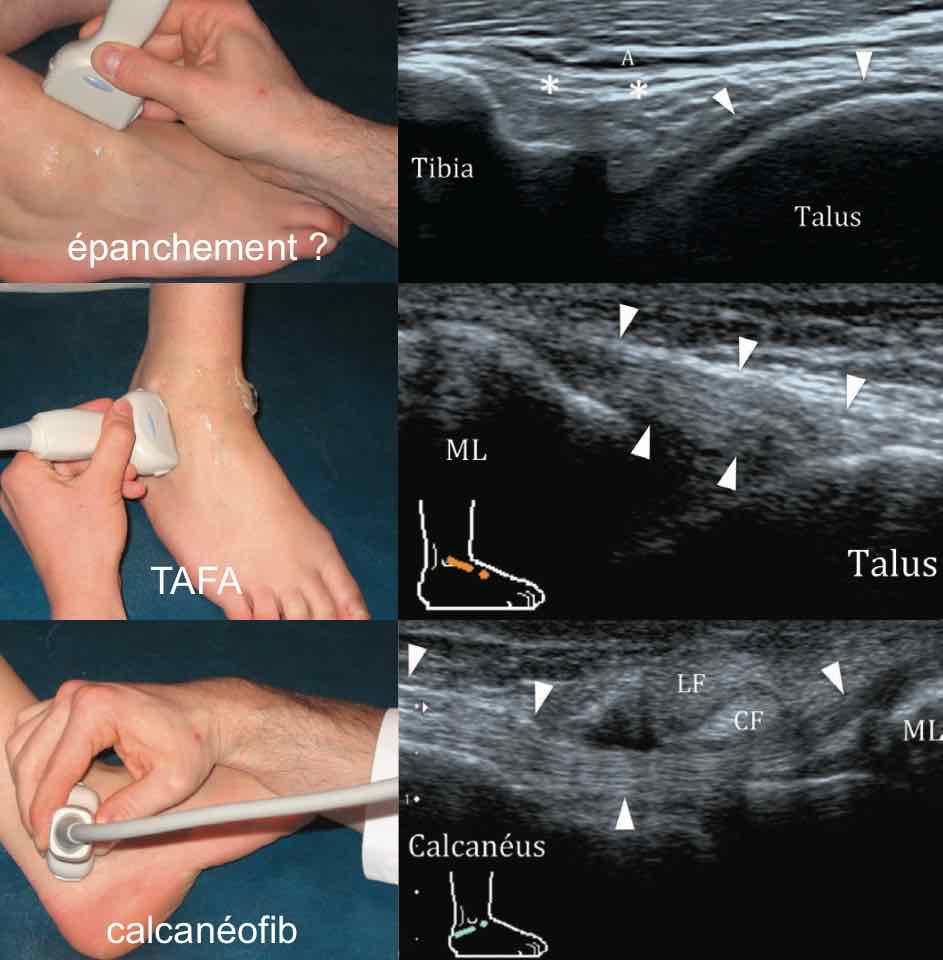

Entorse

Pas d'épanchement dans l'articulation tibio-talienne.

Aspect normal des ligaments talofibulaire antérieur et calcanéofibulaire.

Respect des ligaments talonaviculaire dorsale, tibiofibulaire antéro-inférieur et calcanéocuboïdien latéral.

Comblement graisseux hyperéchogène sans particularité du sinus du tarse.

Tendons court et long fibulaires en place, sans épanchement.